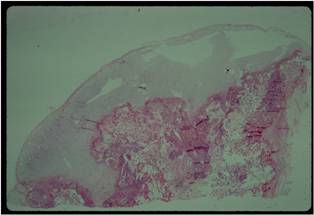

Pathology:

- Medullary and cortical continuity w/ underlying bone

- Hyaline Cartilage Cap with lobular growth

Gross Pathology

- The osteochondroma is completely covered in periosteum

- Cut surface shows hyaline composition of cartilage cap

Beneath the cap, calcified cartilage which appear as white deposits are present

Microscopic Pathology